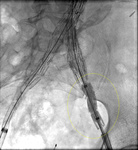

Extension stent graft deployed for the same type I endoleak (encircled)

University of Michigan, specifically the cases of Dr Upchurch reflecting the Departments of Vascular Surgery and Radiology